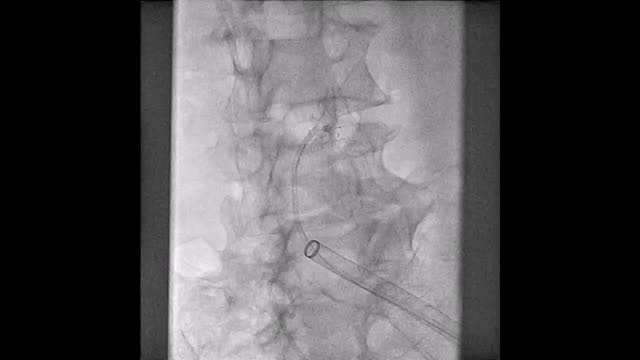

El paciente se traslada a la sala de hemodinamia donde se intenta la extracción del dispositivo. Se utilizan diferentes catéteres lazo de 10, 25 y 30 mm, así como lazos de fabricación con guías largas y cortas intentando movilizar el dispositivo desde diferentes accesos vasculares (acceso bifemoral 6 y 18 Fr y radial 6 Fr) (figuras de la 1 a la 4). Se produce como complicación disección de aorta abdominal con extensión a arteria ilíaca común derecha (figuras 5 y 6) y pérdida total del flujo en extremidad inferior ipsilateral con signos y síntomas de isquemia arterial aguda, por lo que el paciente es trasladado de forma urgente al quirófano de angiología y cirugía vascular. Se realiza disección de aorta abdominal infrarrenal vía laparotomía media con aortotomía longitudinal en el lugar de la localización del cuerpo extraño visualizándose el dispositivo migrado anclado a la íntima-media de la pared arterial. Se procede a su extracción y posteriormente se realiza cierre de aortotomía con parche de pericardio bovino fijando la disección y corrigiendo así el defecto (figuras de la 7 a la 9). El paciente sale de quirófano con pulso pedio bilateral y excelente perfusión distal.